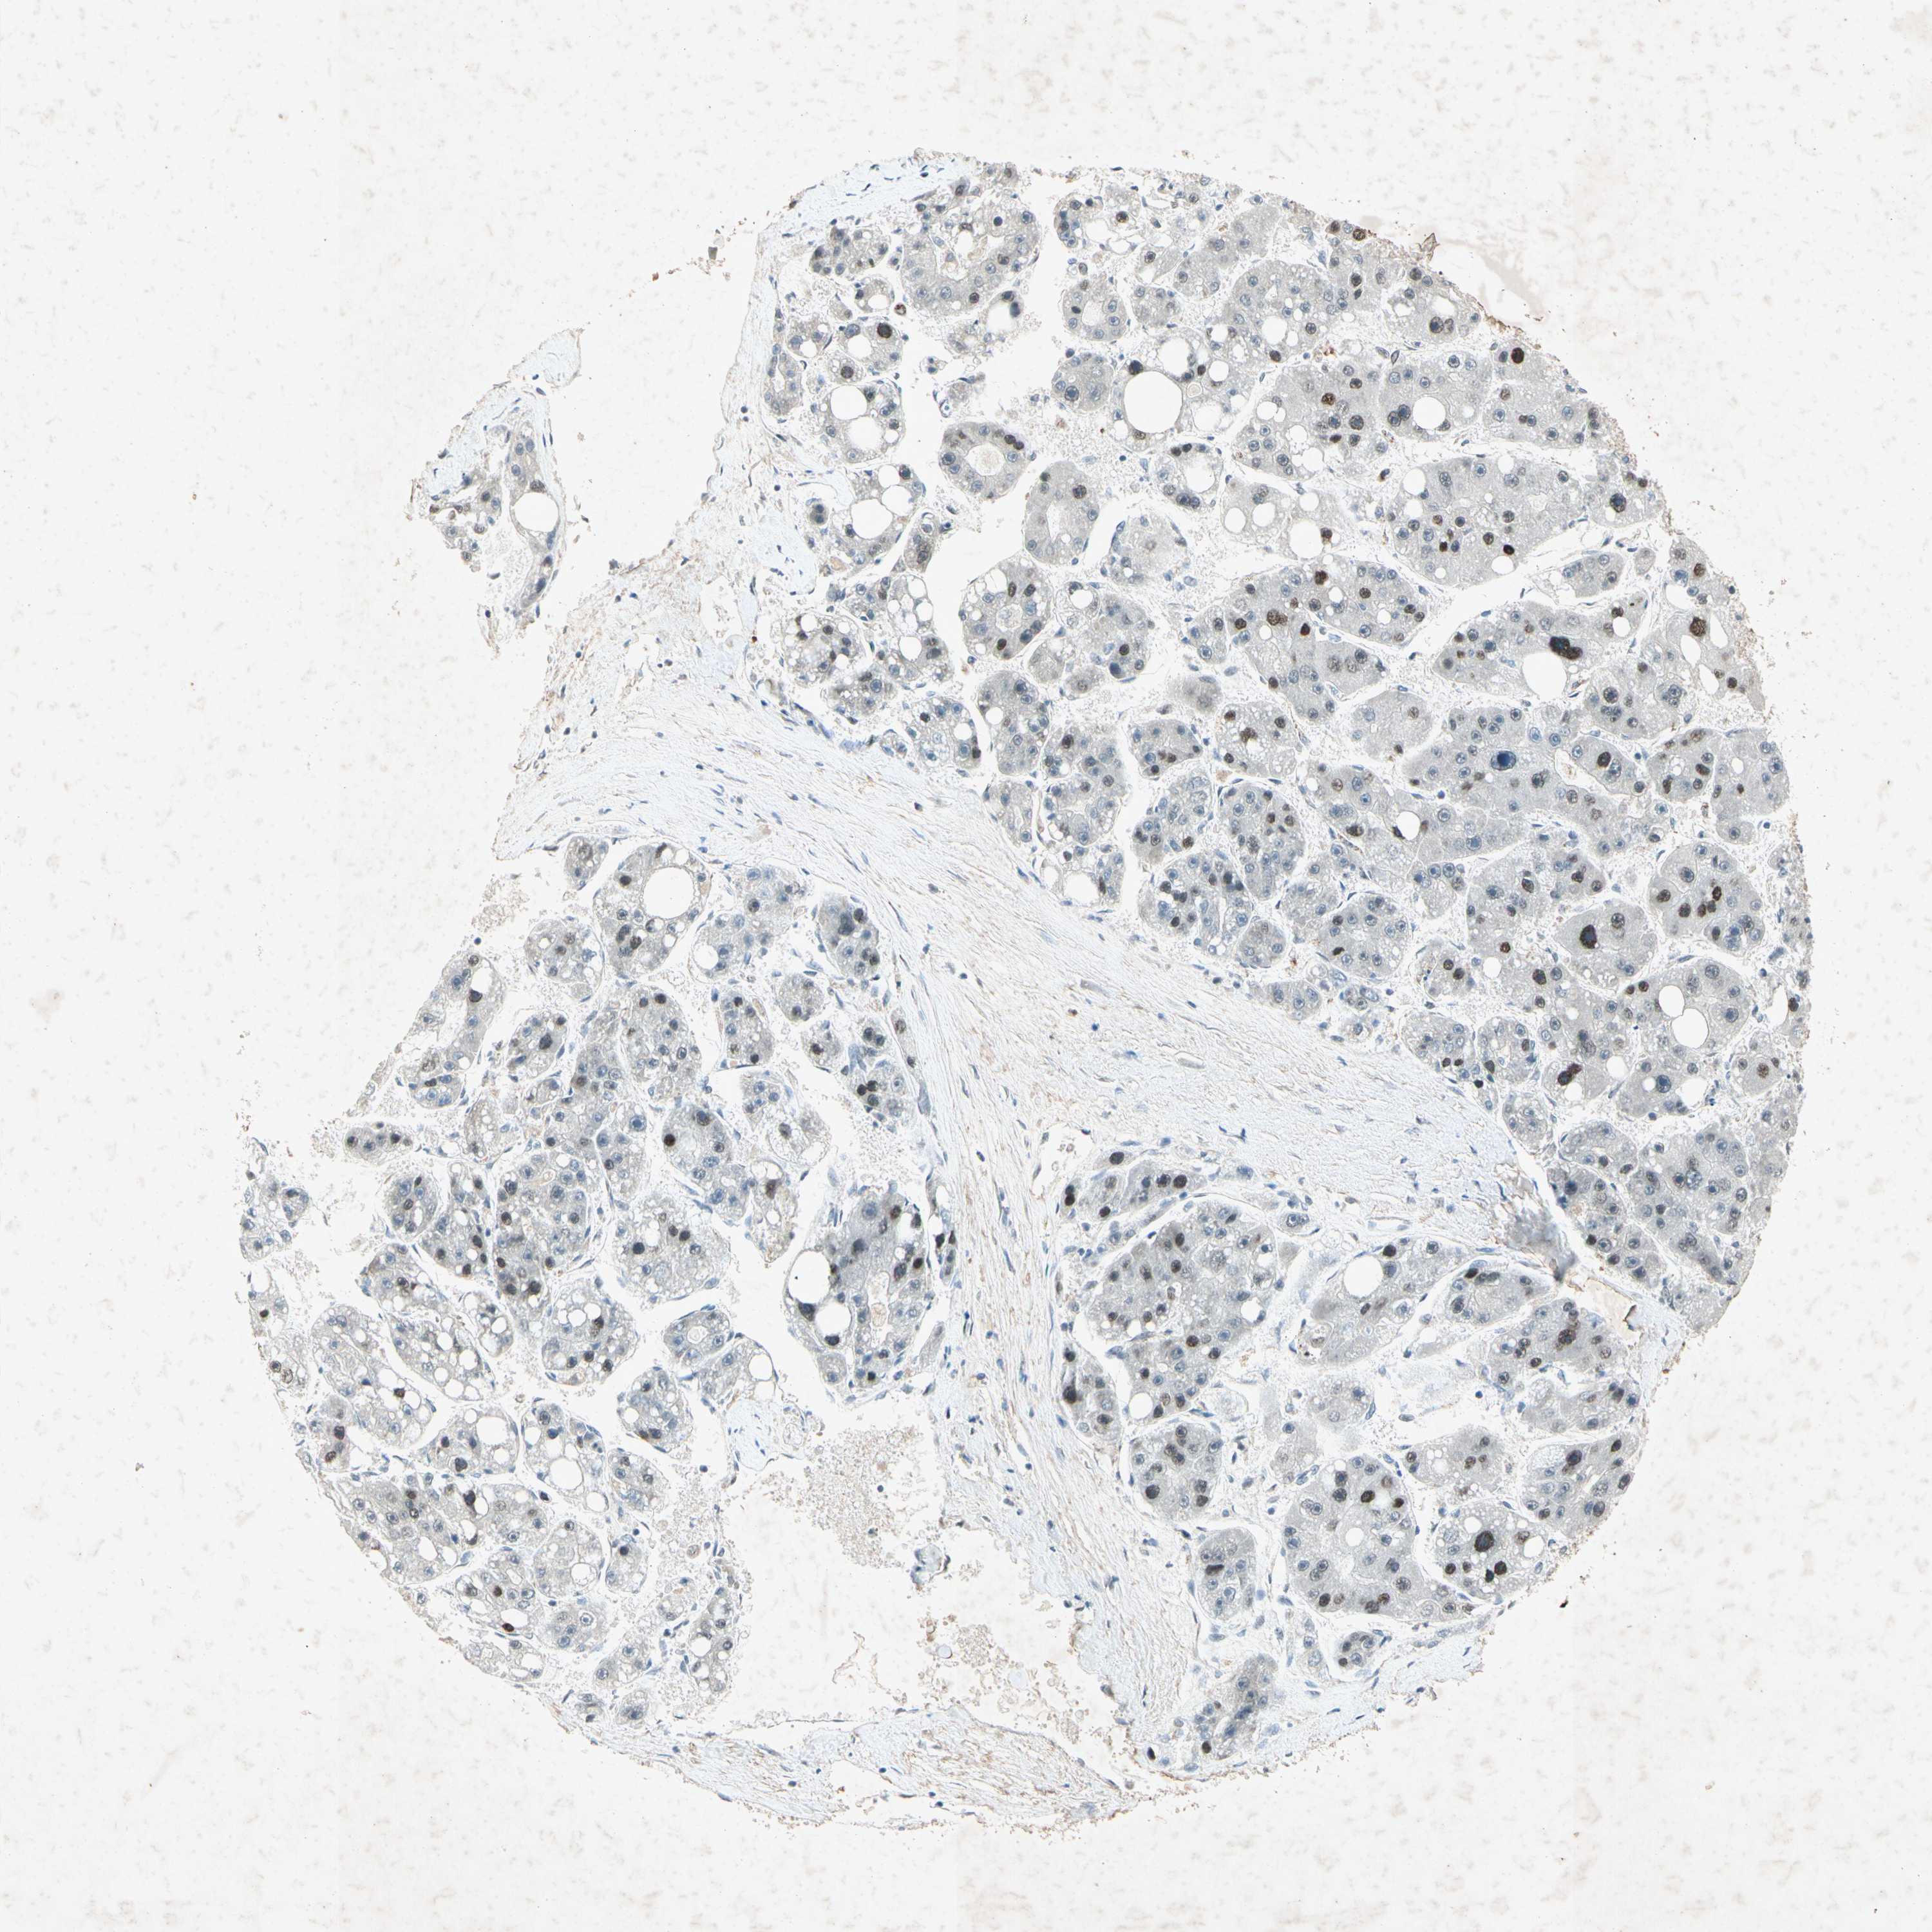

RNF43